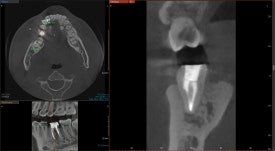

20250127

CT를 찍어봅니다.

아니나다를까,

뿌리 끝에 검은 빈 공간이 관찰됩니다.

염증 물질로 인해 뼈가 녹은 흔적입니다.